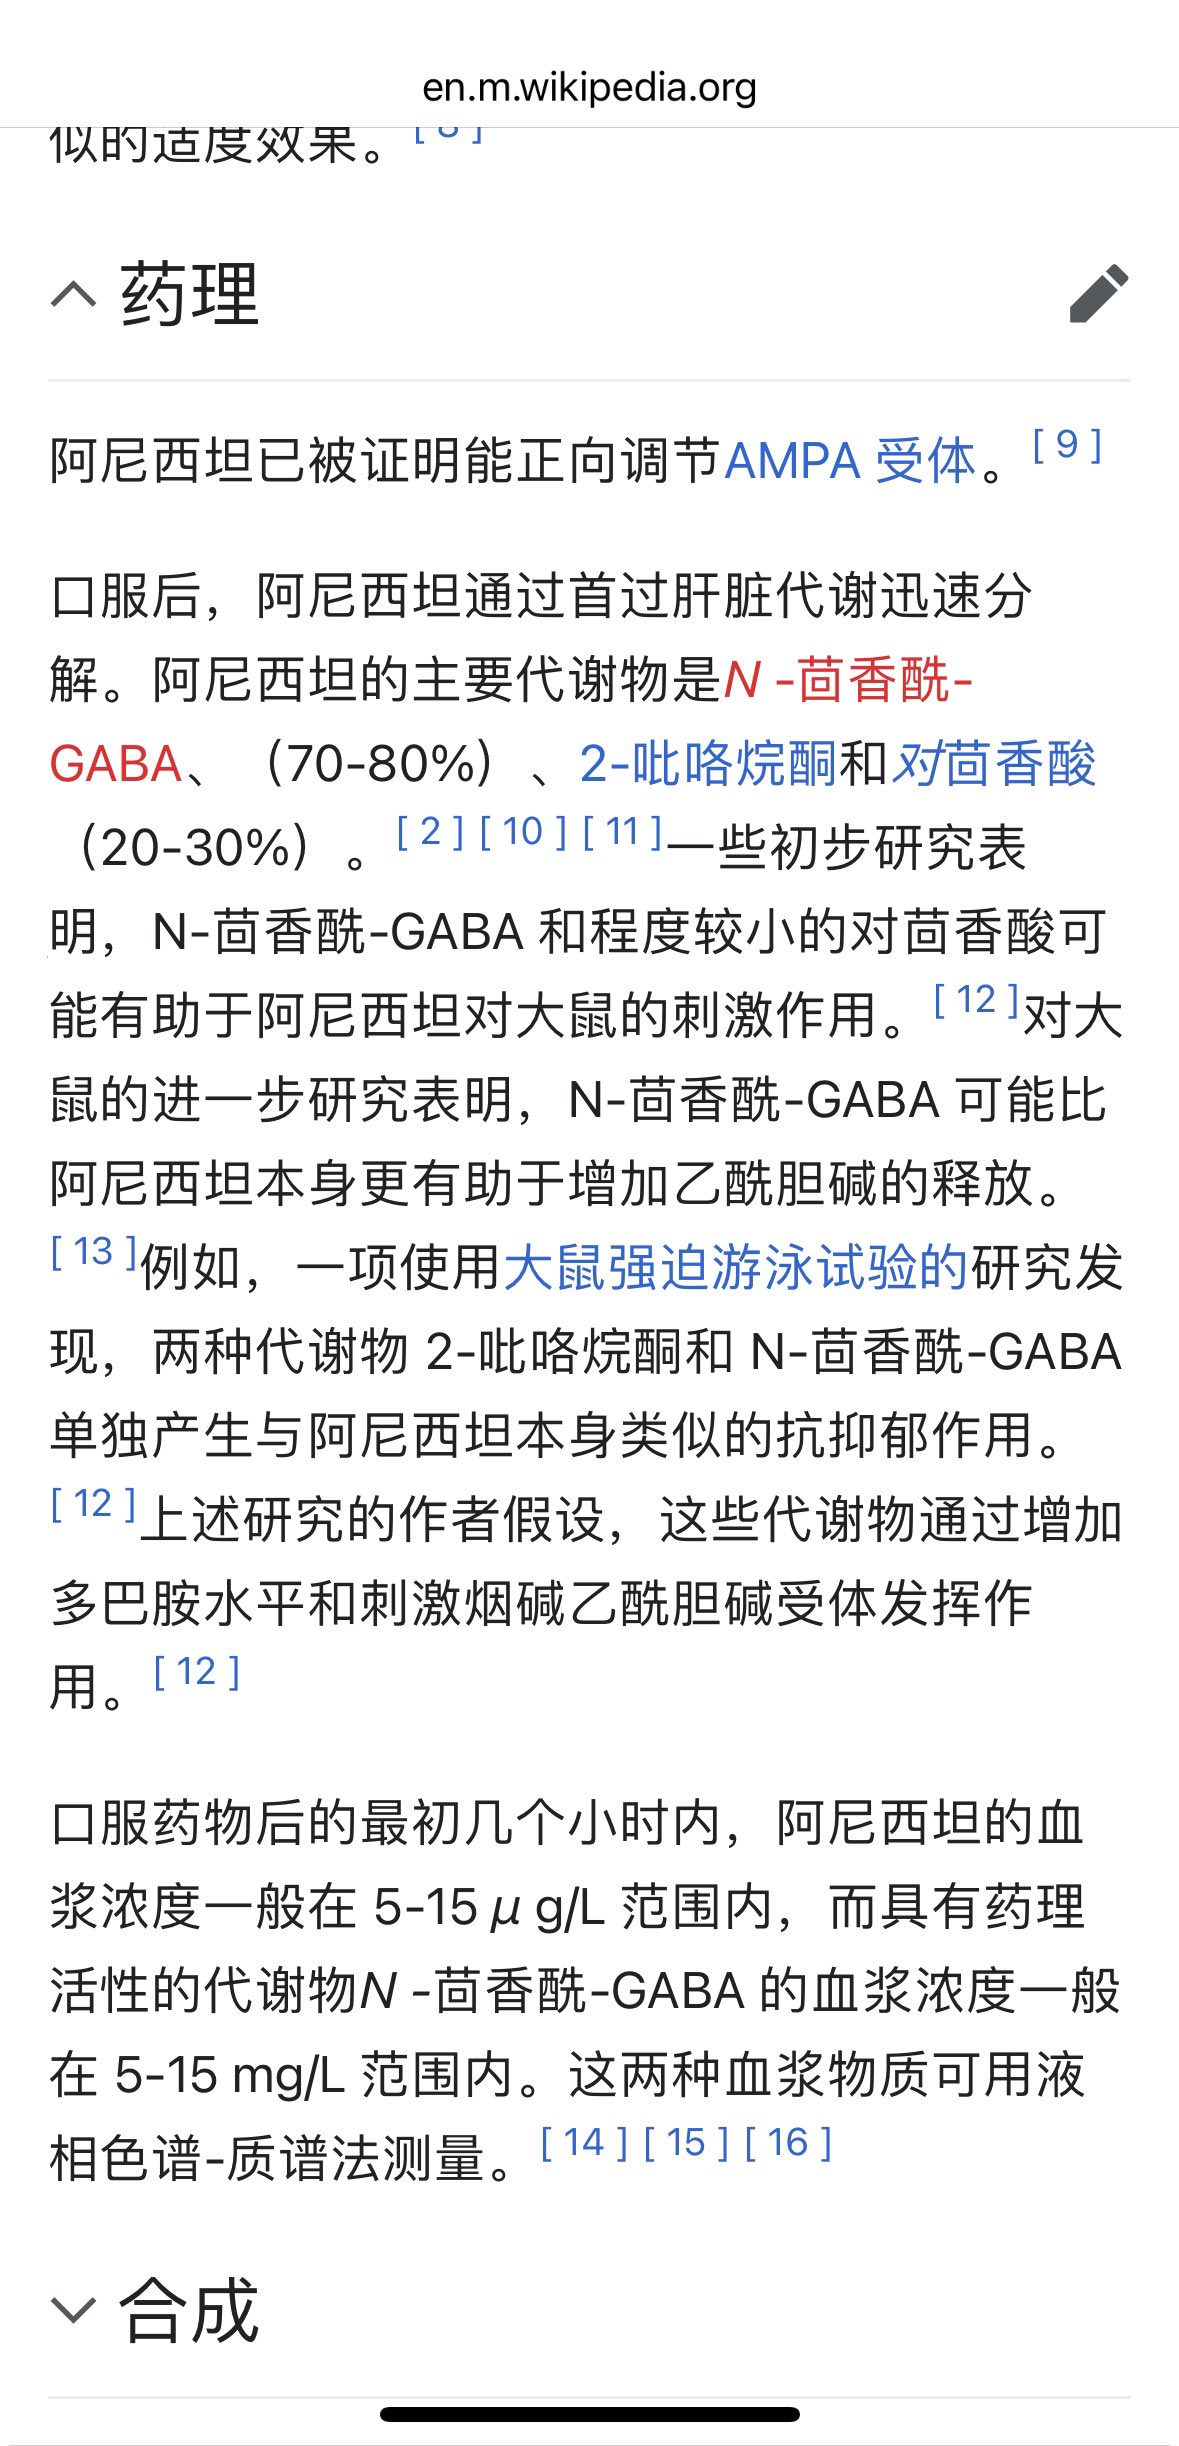

首先,从定义上讲,“反解离(anti-dissociative)”并不是一个标准的医学术语或者广泛认同的药理学分类。在正规资料,比如医学文献、维基百科、精神药理学教科书中,目前并没有“反解离药物”这个正式概念。

看上去像是为了描述某类特定效应而创造的术语(可能是nmda受体活性增强),用来对抗因NMDA受体拮抗剂(比如氯胺酮、DXM、PCP等)引发的解离体验(dissociation)。

那么更常见的是将其归入认知增强剂(cognitive enhancers),特别是改善认知连接性(connectivity)和现实感知(reality testing)的类型。

但其实在药理学上,单纯用“受体激动剂”来逆转“受体拮抗剂”的效应,有时会导致过度激活。

对于NMDA受体而言,过强的NMDA活化本身就与兴奋性毒性(excitotoxicity)和精神病样症状(psychotomimetic effects)有关,比如谷氨酸风暴可以引发严重的焦虑、妄想、乃至癫痫。

也就是说,简单地“激动-解除拮抗”在中枢神经系统是很危险的做法,尤其是对于易感个体(如有精神分裂素质的人)。

科学的处理方式一般是通过更细致的调节,比如微调NMDA/AMPA平衡、调节其他辅助途径(如GABA、5-HT、mGluR受体),而不是简单粗暴地用“NMDA增强剂”去顶回去。

而临床处理药物中毒中,其实医生更常用的做法是保守、支持性的治疗,比如补液,促进代谢,必要时镇静,以及监测生命体征防治并发症。

药物拮抗与受体激动之间,往往牵扯到的是复杂的适应性变化(receptor upregulation/downregulation),

不是简单的“给多一点刺激就能抵消”的关系